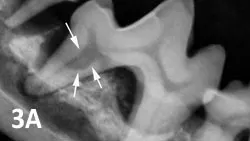

Internal surface resorption (See Figure 3A), is characterized by an oval-shaped enlargement in the apical third of the root canal, interpreted as a sign of active revascularization and considered a self-limiting process that results from mild traumatic injuries.

A dental radiograph showing a canine tooth with arrows indicating areas of periodontal disease, highlighting bone loss around the roots. The image provides a clear view of the tooth structure and surrounding alveolar bone.

Figure 3A

Mandibular first molar distal root with evidence of internal resorption and periodontal disease (arrows).